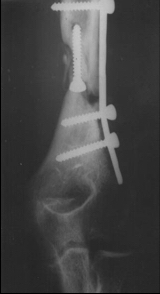

2. Lecco kliniğinin geliştirdiği hibrid sistem en güvenli tespit metodudur. Buna göre suprakondiler bölgede uygulanan 2 adet stoplu K –teli dışında bütün tespitte lateral ve antero lateralden uygulanan Schanz vidaları kullanılmaktadır.

3. Paley ve arkadaşları distal humerusda her iki kondilden çapraz yollanan 2 adet Schanz vidasını stabil bir tespit olarak belirtmektedir. Klinik uygulamalarımıza göre medialden Schanz vidası tespiti yapılmadan ulnar sinir eksplorasyonu kanımca en güvenli yoldur.

7. Distal tespitlerde metal çember kullanılıyorsa yarım halka, dirseğin anteriorunu açık bırakacak şekilde yerleştirilmelidir. Eğer karbon çember kullanılıyorsa ameliyat bitiminde dirsek ROM’una izin verecek şekilde anterior kesilerek serbestleştirilmelidir.